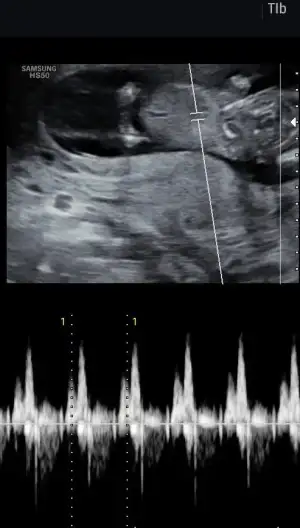

Merhabaaaa , 12. Haftada erkek dedi ama beni hep hissim kızdıı en önemlis sağlıklı olması tabiki ama ama içim içimi yiyiyor doktor emin ama ben emin olamıyorum :) bi bakabilirmisiniz böyle birşey yaşayan varmı?

8D8B5252-A5B6-48D2-B9F4-F1DB57A8A20D.webp

633BD55A-1707-4AEB-9744-8E18CB5E9F3B.webp

0F34E68A-5766-4A2F-8A9C-A0E5C7DF57A7.webp

8D8B5252-A5B6-48D2-B9F4-F1DB57A8A20D.webp 633BD55A-1707-4AEB-9744-8E18CB5E9F3B.webp 0F34E68A-5766-4A2F-8A9C-A0E5C7DF57A7.webp